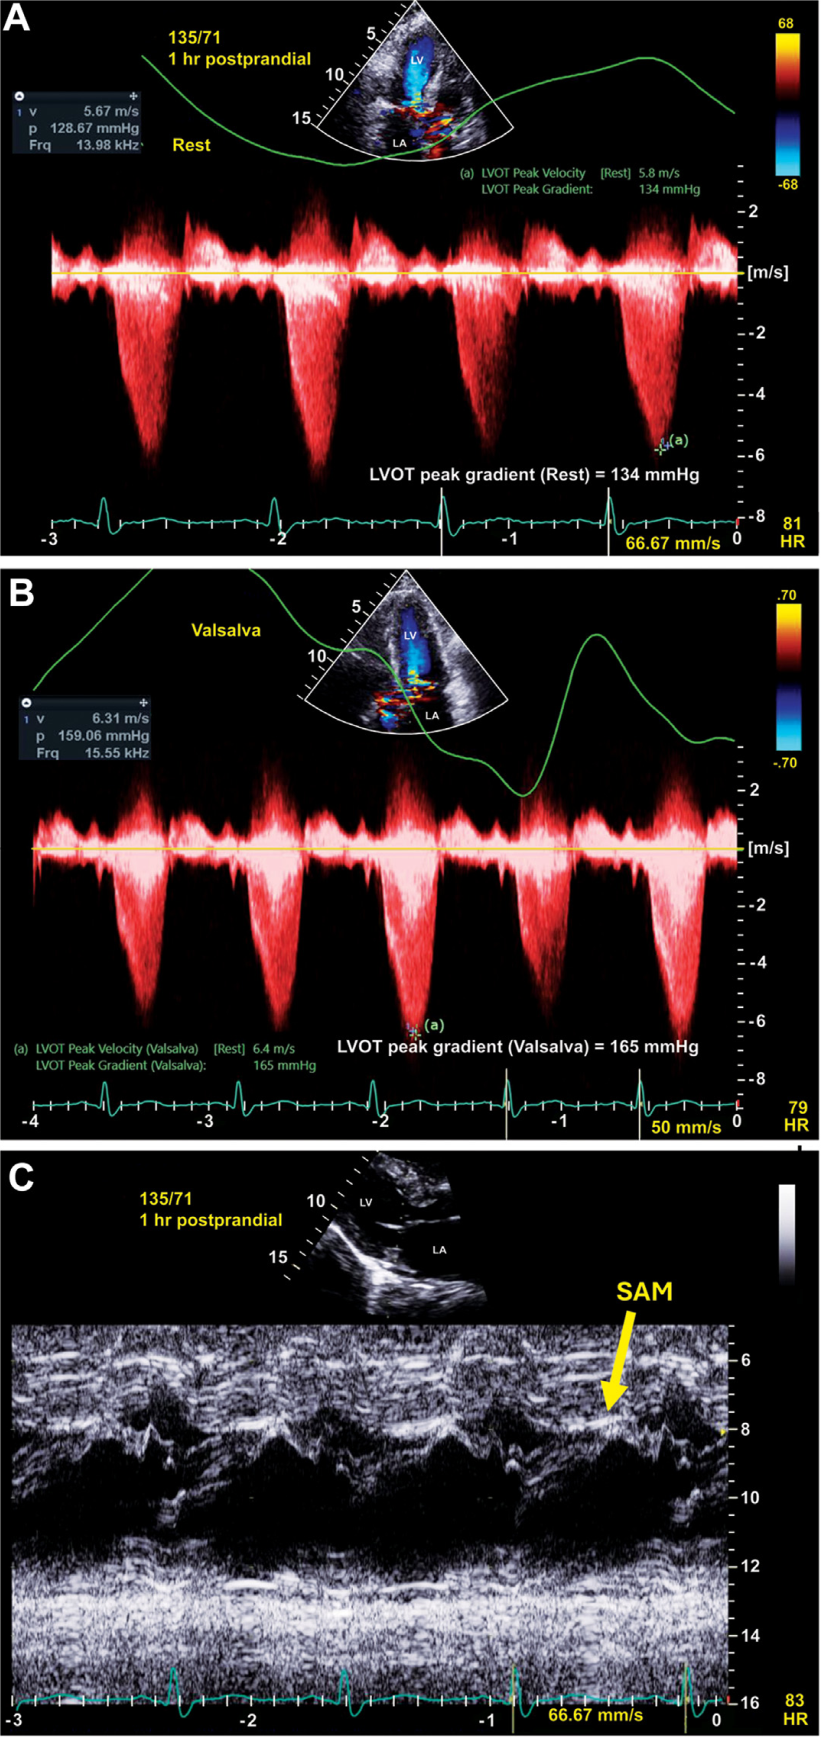

术后患者出现短暂低血压(持续<12小时),通过低剂量去氧肾上腺素即可纠正。次日拔管,改鼻导管吸氧。尽管初期血流动力学改善,但ASA后1周超声示LVOTO复发,腱索SAM及中度二尖瓣反流(图6)。出院(术后第12日)时,患者病情稳定,口服美托洛尔75mg每日两次、维拉帕米120mg每日一次。

图6 术后1周经胸超声

(A)静息LVOTO 134mmHg;(B)Valsalva动作时 165mmHg;(C)M型超声显示二尖瓣腱索SAM(黄箭头)。